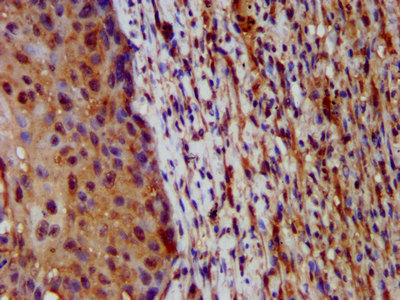

IHC (Immunohistochemistry)

(IHC image of AAA234571 diluted at 1:200 and staining in paraffin-embedded human liver tissue performed on a Leica BondTM system. After dewaxing and hydration, antigen retrieval was mediated by high pressure in a citrate buffer (pH 6.0). Section was blocked with 10% normal goat serum 30min at RT. Then primary antibody (1% BSA) was incubated at 4 degree C overnight. The primary is detected by a biotinylated secondary antibody and visualized using an HRP conjugated SP system.)